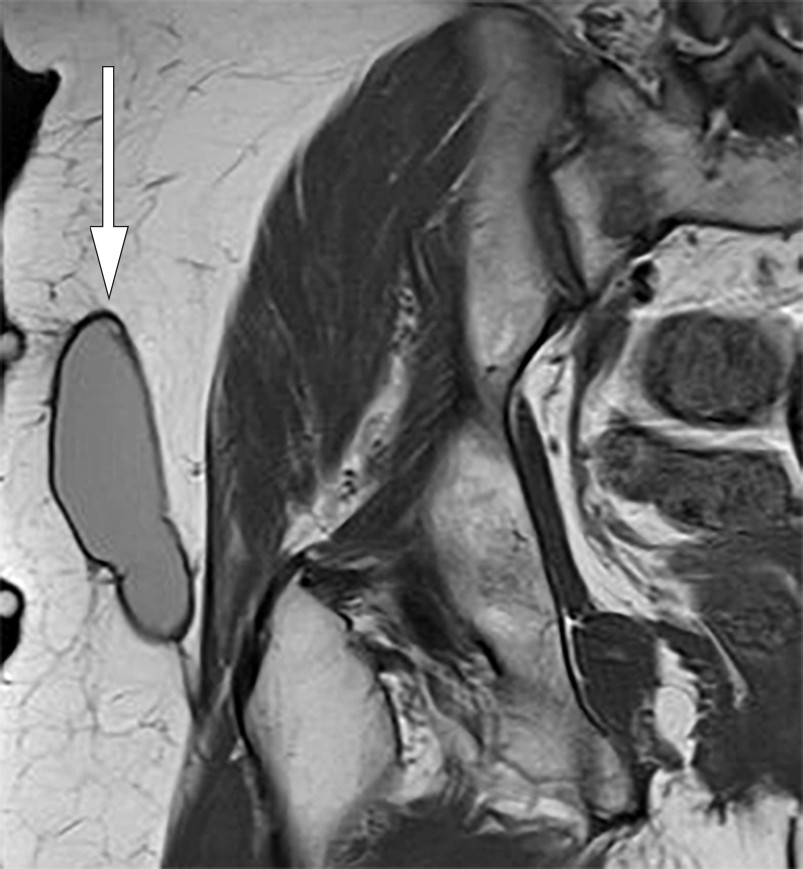

No recurrence was seen at four-week follow-up. The patient felt only mild discomfort in the area and was able to discontinue compression. At 12-week follow-up, MRI of the right hip showed almost full regression of the lesion (Figure 2). At one-year follow up, the patient showed no clinical or radiographic evidence of disease, but with sequelae in the form of mild skin contraction.

Figure 2 Coronal T1-weighted MRI of right hip. Minor residual changes after previous fluid-filled locule.